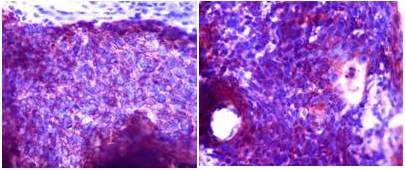

La revisión realizada por servicio de anatomía patología de nuestro centro, evidencia un nódulo con capsula fibrótica que muestra en su interior un carcinoma de células escamosas de aspecto basaloide con áreas sólidas y quísticas (Figura 5).

No observan tejido ganglionar linfático remanente, por lo que infieren que los hallazgos son compatibles con neoplasia primaria originaria de un quiste branquial complementando con realización de estudio de inmunohistoquímica, el cual resultó positivo para citoqueratina 34BE12, P63 y citoqueratina 7.